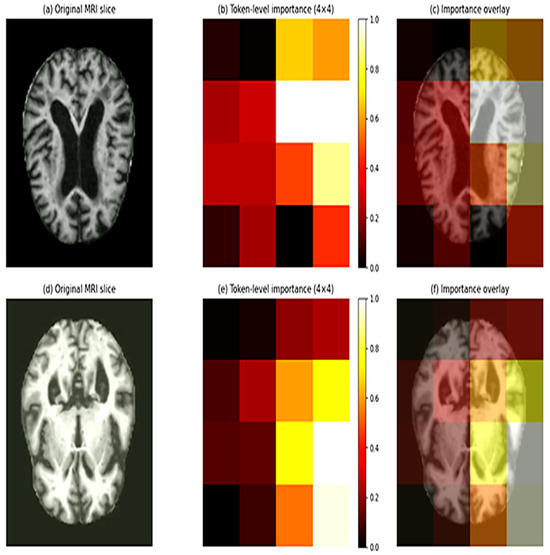

Progression-Aware and Explainable CNN–Transformer Framework for Multiclass Alzheimer’s Disease Staging Using MRI

Background: Alzheimer disease (AD) is a neurodegenerative condition that progressively develops structural changes in the brain, resulting in different stages of severity, which makes accurate multiclass classification from magnetic resonance imaging (MRI) challenging. Despite promising outcomes of deep learning models, a great number of current methods disregard disease progression, suffer from evaluation leakage, or lack interpretability. Objectives: This paper introduces DeepAttentionADNet, a lightweight hybrid CNN–Transformer framework designed for multiclass staging of Alzheimer’s disease using MRI images. Methods: The proposed model integrates convolutional feature extraction with transformer-based global context modeling. To capture the ordered nature of disease severity, a progression-aware ordinal learning objective is proposed. Moreover, consistency regularization is utilized to enhance robustness by imposing consistent prediction with spatial perturbation. A leakage-free k-fold cross-validation protocol is adopted, in which data splitting is performed prior to augmentation. Also, to promote interpretability, token-level importance maps based on transformer embeddings are utilized to visualize spatial regions that were used to make classification decisions. Results: The experimental findings on a multiclass MRI dataset of Alzheimer disease demonstrate consistent and high performance across cross-validation folds (mean F1-score (0.991 ± 0.003) and AUROC (0.9998 ± 0.0002)), without losing transparency and progress awareness. Conclusions: The proposed framework provided a robust and interpretable method of Alzheimer disease severity classification using MRI. Full article